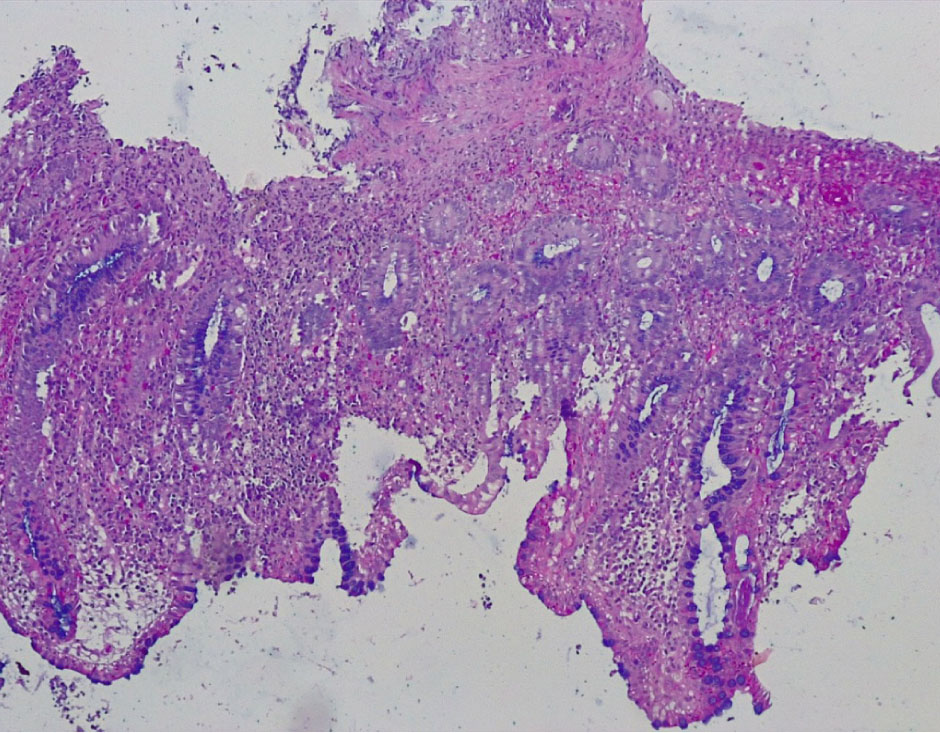

В отдельных группах крипт отмечалось выраженная атрофия бокаловидных клеток (БК) (не более 3–4 на крипту) вплоть до полного их исчезновения (+++), развитие очагов гнойного криптита за счет выраженной нейтрофильной инфильтрации вокруг крипт (рис. 4).

Окраска на слизь выявила почти полное исчезновение слизи на поверхности цилиндрического эпителия СО и в большинстве крипт за счет резко выраженной атрофии бокаловидных клеток (не более 4–5 БК на крипту) (+++) (рис. 5).